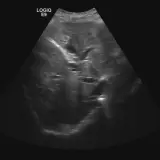

Casos totalmente interactivos con las herramientas que esperaría de un PACS: scroll, ventana, zoom, pan, mediciones, ROI y modo de pantalla completa.

Desplace, arrastre, ajuste ventana y amplíe como en una estación PACS de trabajo